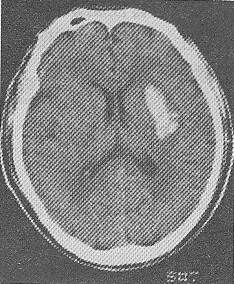

| 正確答案:D 解題思路:試題難度:中,本題考查目的是綜合臨床資料和CT圖像作出腦血管的診斷。從上題的腦缺血性卒中與腦出血性卒中的鑒別要點(diǎn)表中很容易得出標(biāo)準(zhǔn)答案D腦血栓形成。短暫性腦缺血發(fā)作的體征一般1~2小時恢復(fù),而且以單肢癱等局限體征為多見。CT圖像上一般沒有梗死灶。腦栓塞一般在活動狀態(tài)下,數(shù)秒鐘即出現(xiàn)明顯腦癥狀,大多數(shù)患者有房顫等栓塞灶的來源。這些均與本例不符合,故缺血后卒中以腦血栓形成為正確答案。 |

正確答案:B 解題思路:試題難度:中,本題考查目的是綜合臨床資料和CT圖像作出腦血管病的診斷。本病例為急性起病的腦血管疾病。腦血管病分為缺血性卒中和出血性卒中。腦血栓形成、短暫腦缺血發(fā)作、腦栓塞均為缺血性卒中范疇;高血壓性腦出血為出血性卒中;根據(jù)腦缺血性卒中和腦出血性卒中的鑒別診斷表(下表),可以得出B,高血壓性腦出血為正確答案。腦轉(zhuǎn)移癌起病較慢,而且CT的病灶周圍有大片水腫,為迷惑答案。